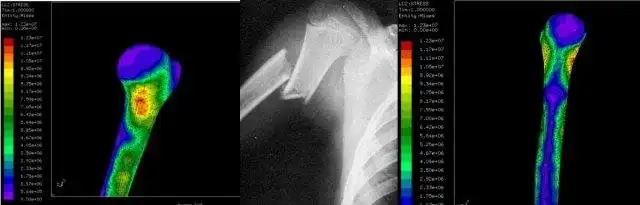

Investigacion de diseño avanzado en biomecanica computacional con elementos finitos usando herramientas de software-libre.

- Advanced design on mechanical engineering.

- Use of high performance,finite element tools, based on software-libre

Science/Research, Education, Engineering